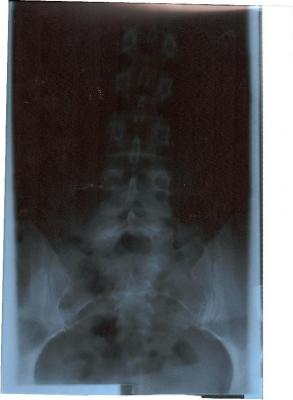

Ach so bevor ich vergesse: von meinem Rücken bestehen 4 Röbis, die den gesamten Rücken zeigen. Das Bild von der LWS ist eigenartig: erst unten gerade und dann geht sie schräg nach rechts hoch. Meine Orhopädin meint, die LWS sei kerzengerade, der FA aus Bochum meint, da hätte ich beim der Aufnahme einen Druck von links bekommen (ich stand aber allein und - für mich - gerade vor dem Gerät. Mich hat nichts und niemand gedrückt - interessiert die Ärzte aber nicht). Leider konnte ich dem Menschen in Bochum auch nur die zeigen, da die CD`s noch im Krankenhaus unterwegs sind.

Die Röntgenbilder habe ich nochmal reingestellt. Sorry, das mit dem Bild verkleinern wusste ich nicht. Ich hab die Bilder zwar in der falschen Reihenfolge eingestellt, aber ich hoffe, dass das nicht tragisch ist: zuerst also das untere Bild (mit Becken), dann das obere für den weiteren Verlauf. Alles wieder im Testforum!

Zum zum Röbi an sich: Es ist wirklich komisch, wie schief das nach oben geht. Ich vermute daher, dass deine eigentliche Krümmung darüber, also in der BWS sitzt oder du eine langgezogene Krümmung hast, die in der BWS weitergeht und dann wieder zur Mitte geht. Aber genau deshalb braucht man eine Ganzwirbelsäulen-Aufnahme!!

ich wollte erst schauen, ob das mit den Bildern funktionert - daher Testforum. Der erste Versuch ist ja auch schief gegangen, doch im Testforum problemlos löschbar. Jetzt hat es geklappt, daher habe ich sie jetzt auch hier. So können sich auch andere dazu äußern (obwohl Deine Meinung schon sehr fachfraulich klingt und ich fast glaube, dass mein Schicksal besiegelt ist!!!). Jedenfalls tut es mir gut, dass jemand anderes auch meint, dass meine WS eben doch nicht kerzengerade aussieht - ich freue mich (dachte nämlich schon, ich wäre bekloppt).

es wäre wirklich interessant, wie deine Wirbelsäule im Ganzen aussieht. In der LWS hast du zumindest schonmal keine Rotation, was positiv ist. Evtl. ist es ja nur eine Fehlhaltung oder eben eine typische Begleit-Skoliose bei Rundrücken. Deshalb ist auch ein seitliches Röntgenbild zur Diagnostik notwendig.Jedenfalls tut es mir gut, dass jemand anderes auch meint, dass meine WS eben doch nicht kerzengerade aussieht - ich freue mich (dachte nämlich schon, ich wäre bekloppt).